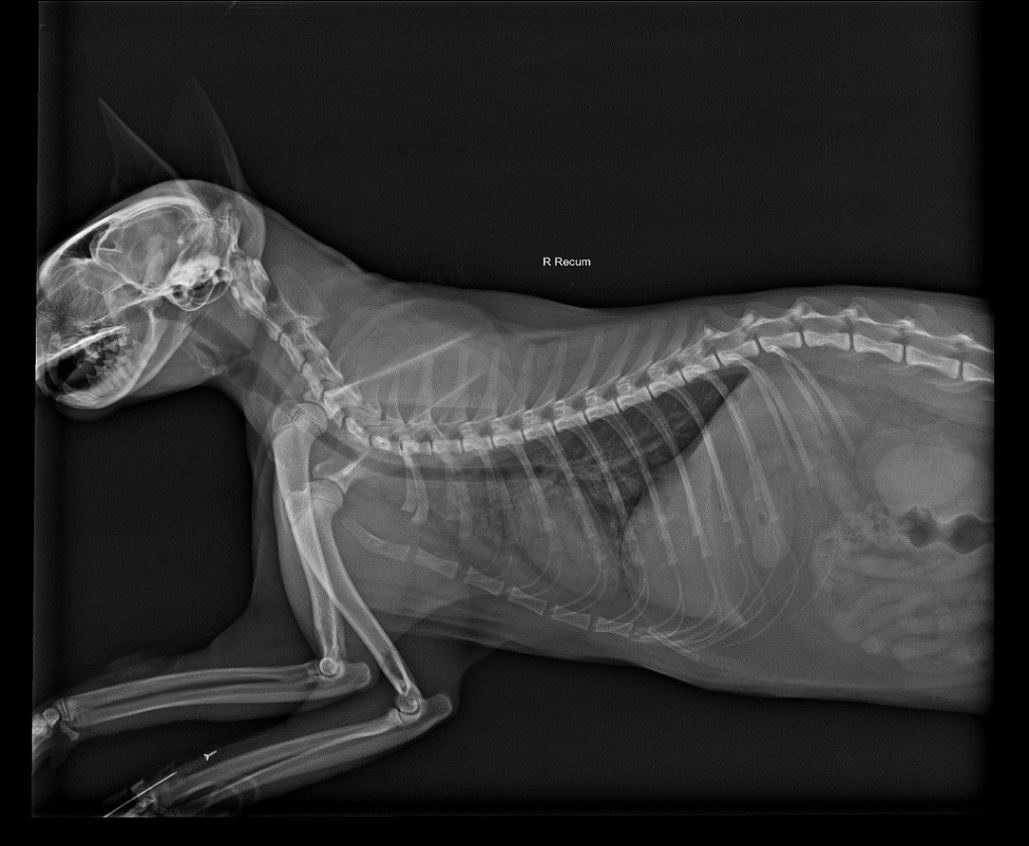

主題: 車禍被肇事逃逸的白白 申請者姓名: 蔡郁婷 花色: 申請日期: 2016-05-20 20:14:20 申請者部落格: 申請者臉書網址: 所在縣市/合作醫院: 高雄市/恩澤動物醫院 治療費用: 20000元 需求人數: 43人 已結案 (2024-06-01 13:36:45) 報名人員: Kari(已付款)、edward(已付款)、HI HI Little(已付款)、蔡美娟 x2(已付款)、Derek(已付款)、徐雅嬪(已付款)、Tina Nai-hui Pan x2、Tina Nai-hui Pan x2(已付款)、尖牙小貓咪(已付款)、Kuo Kuo Kuo(已付款)、Q(已付款)、Vaporxu Liu x2(已付款)、王琇(已付款)、GU GU x2(已付款)、Yun Lin(已付款)、GreenFire(已付款)、暢暢(已付款)、Alyson Wu(已付款)、Eric Chien(已付款)、Hllen Liu(已付款)、Ray0322(已付款)、Lei Zang(已付款)、李庭芝(已付款)、Sarah Xie(已付款)、Mia Chao(已付款)、林廷軒(已付款)、Jasmine Lin(已付款)、李冠愉(已付款)、鳥蛋、Yi-Ling Yao x2(已付款)、Yi-Ling Yao x2、Lei Zang(已付款)、Y.Y. x2、小可(已付款)、vivian(已付款)、Patrick x2(已付款)、kimi-hsu x2(已付款)、clement(已付款)、a-song x2(已付款)、 候補人員: 動物病情說明: 4/25騎車回家的路上發現貓咪躺在路上不走,右眼極度突出,又漏尿,研判是發生車禍,於是先送往24小時的高雄中興大豐總店,隔天4/26中午轉院恩澤動物醫院

經醫生診斷,右眼失明,右腳骨折,肋骨斷裂兩根,下顎骨折。

因無法禁食插了食道胃管,剛開始因腦部撞擊,不能做骨折手術,先將右眼縫合,避免感染,只能先以維持生命跡象為主,持續住院觀察經過一周才做骨折手術

5/9做骨折手術,原定5/16出院,但因傷口癒合未達標準,所以延長住院到5/20才出院,